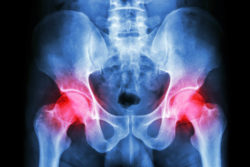

The Stryker Corporation is facing a growing multidistrict litigation (MDL), consisting of product liability claims alleging problems with Stryker metal on metal hip implant modules.

Metallosis and the majority of other complications associated with metal on metal hip implants allegedly stem from the all metal ball and socket components that interact without any kind of interference. This causes metal ions to be shed into the bloodstream, which can develop into metallosis and cause a multitude of other problems including: